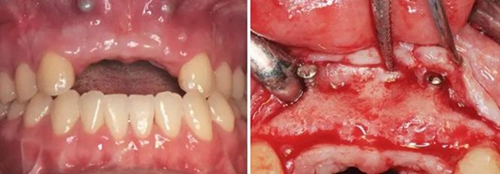

圖11 植骨后6月種植術(shù)前 圖12 種植術(shù)前翻瓣后見少量鈦釘螺紋暴露

圖13 取出鈦釘后 圖14 攜帶體示植體位置方向良好

圖15 種植術(shù)后 圖16 種植后嚴(yán)密縫合創(chuàng)口

(3)2015年2月:Onlay植骨后6月行種植手術(shù)

術(shù)前再次拍攝CBCT,顯示牙槽嵴寬度較植骨當(dāng)日有一定量的吸收,測量可用骨寬度,12位點(diǎn)為3.7mm-10.9mm,22位點(diǎn)為5mm-10.9mm。做術(shù)前準(zhǔn)備,用0.12%的復(fù)方氯己定漱口液含漱3次,每次15ml,含漱1min。采用無痛麻醉機(jī)(STA),復(fù)方鹽酸阿替卡因進(jìn)行口內(nèi)局部浸潤麻醉,將麻醉藥物緩慢注入術(shù)區(qū)的牙槽嵴骨膜下方。翻瓣并剝離粘骨膜后充分暴露牙槽骨,取出先前固定骨塊的鈦釘,確認(rèn)植入位點(diǎn),小球鉆定點(diǎn),使用BEGO骨水平種植體及其配套器械(BEGO公司,德國),根據(jù)擬植入種植體長度以及直徑大小,逐級(jí)備洞,植入2顆種植體,均為BEGO,RSX植體,直徑為3.75mm,長度為15mm,獲得35Ncm以上植入扭矩,用種植體穩(wěn)定性測量儀Osstell ISQ (Osstell公司,瑞典)測量ISQ值:12、22位點(diǎn)種植體均為79,種植體平臺(tái)位于骨下約1mm,術(shù)后上愈合基臺(tái),嚴(yán)密縫合創(chuàng)口。